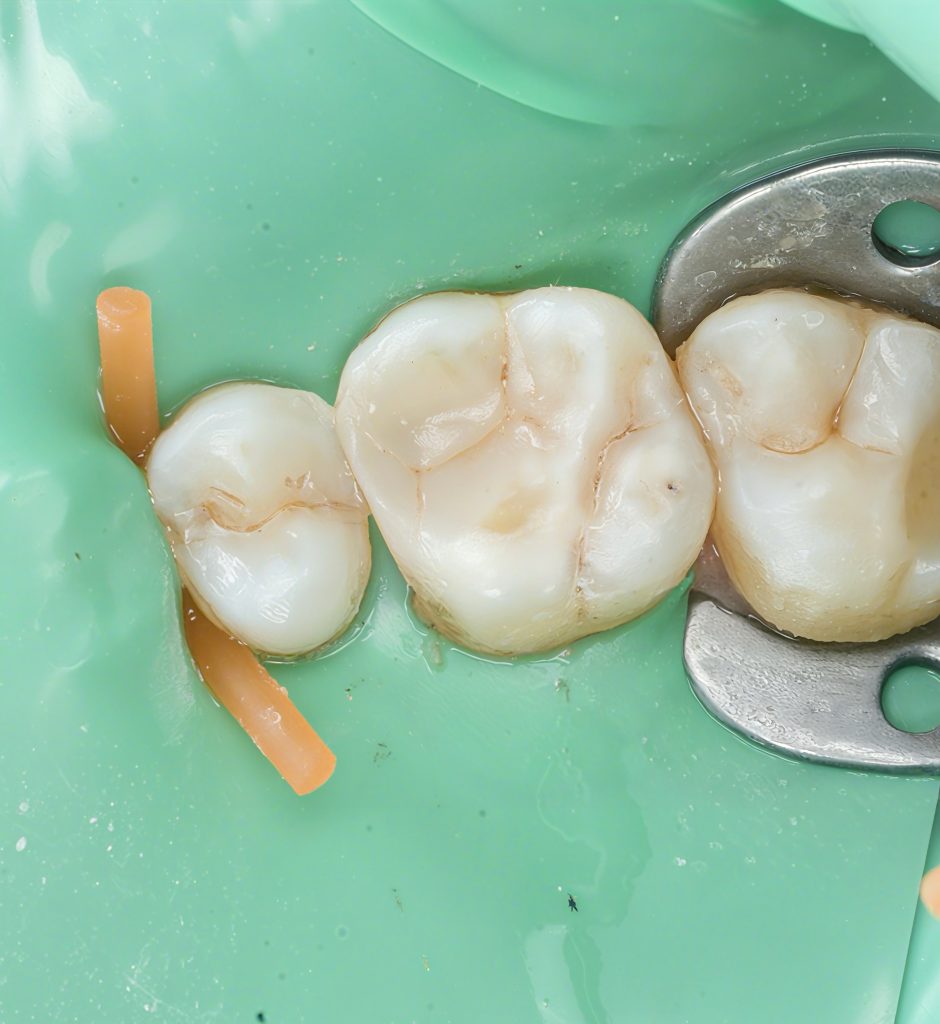

7. Post-op Result

A clean, natural anatomy with:

- A sealed proximal contact

- Proper cusp-fossa relationship

- Smooth margins

- No postoperative sensitivity expected